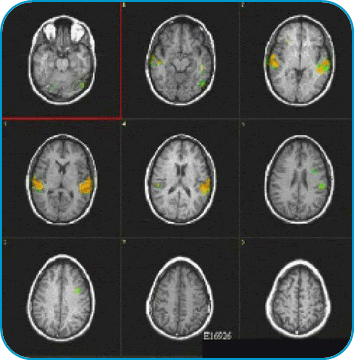

fmri1.png

The areas in color depict the activation of the brain regions involved in hearing and comprehending the human voice. The left hemisphere shows greater activation.